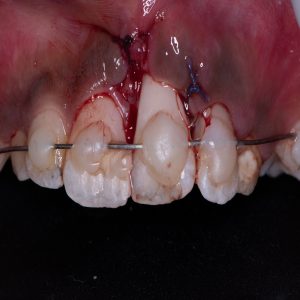

Treatment and Services